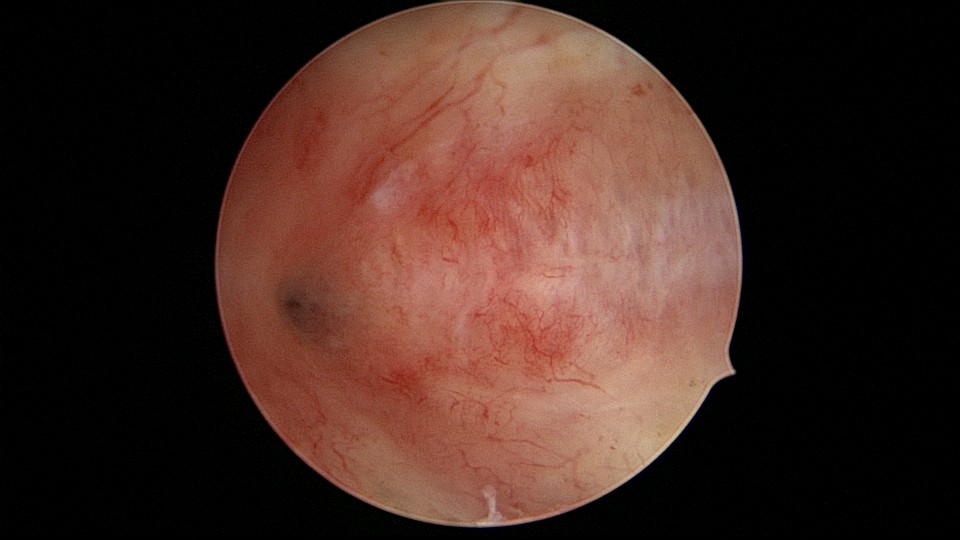

患者28岁,G1P0,2019年11月孕9周胎停1次,药流清宫,术后月经量逐渐减少,淋漓不净。外院B超发现宫腔粘连,2021年6月初宫腔镜探查,宫腔两侧及右侧宫角粘连,单级电针分粘,恢复宫腔形态,显露双侧输卵管开口(术中图像采集系统突发故障,分粘及分粘后图片未采集到)。2021年6月底宫腔镜二探取球囊,宫腔形态正常,双侧输卵管开口可见。2022年12月自然妊娠,足月顺产。现33岁,G2P1。